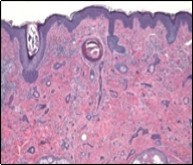

Lesions are generally superficial and infrequently invade lower dermis. Tendency for peri-neural or intra-neural infiltration, cogitated in adjunctive cutaneous carcinomas, is exceptional in desmoplastic trichoepithelioma. Nevertheless, desmoplastic trichoepithelioma can be exemplified as a component of particularly desmoplastic, cutaneous carcinomas demonstrating foci of peri-neural involvement 4, 5. Figure 1, Figure 2, Figure 3, Figure 4, Figure 5, Figure 6, Figure 7, Figure 8.

Figure 4.Desmoplastic trichoepithelioma depicting cords and aggregates of basaloid epithelial cells with encompassing dense, compact fibrous tissue stroma 11.